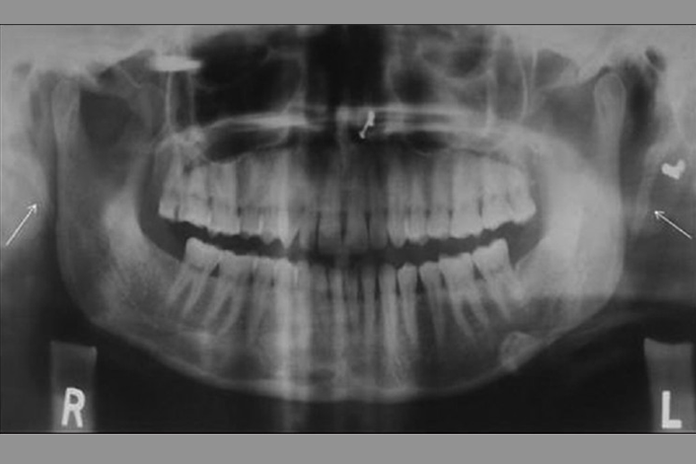

Eagle syndrome is a rare condition where the styloid process becomes elongated or the stylohyoid ligaments become calcified. When the process elongates, it can constrict nerves, the carotid artery, and create a variety of symptoms that are often misdiagnosed. (see Image 1 and 2)

Is the styloid process approximately 2.5cm, or has it elongated? How does the TMJ look? If the styloid process is elongated and the TMJ looks relatively normal, a referral to an ear, nose, and throat specialist (ENT) is advised.

Most symptoms associated with Eagle syndrome are also commonly found symptoms of TMD, making diagnosing Eagle syndrome a little tricky. As a general rule, the dental profession has been taught to evaluate for TMD and treat accordingly. A second review of panoramic images in patients who find little comfort with TMD treatment should be considered. A closer look may reveal an elongation of the styloid process, prompting a referral to an ENT.

However, if your patient has no problematic symptoms and you notice an elongation of the styloid process on panoramic imagery, inform the patient of your finding and advise of the potential for Eagle syndrome symptoms as this discovery in itself does not diagnose the syndrome.